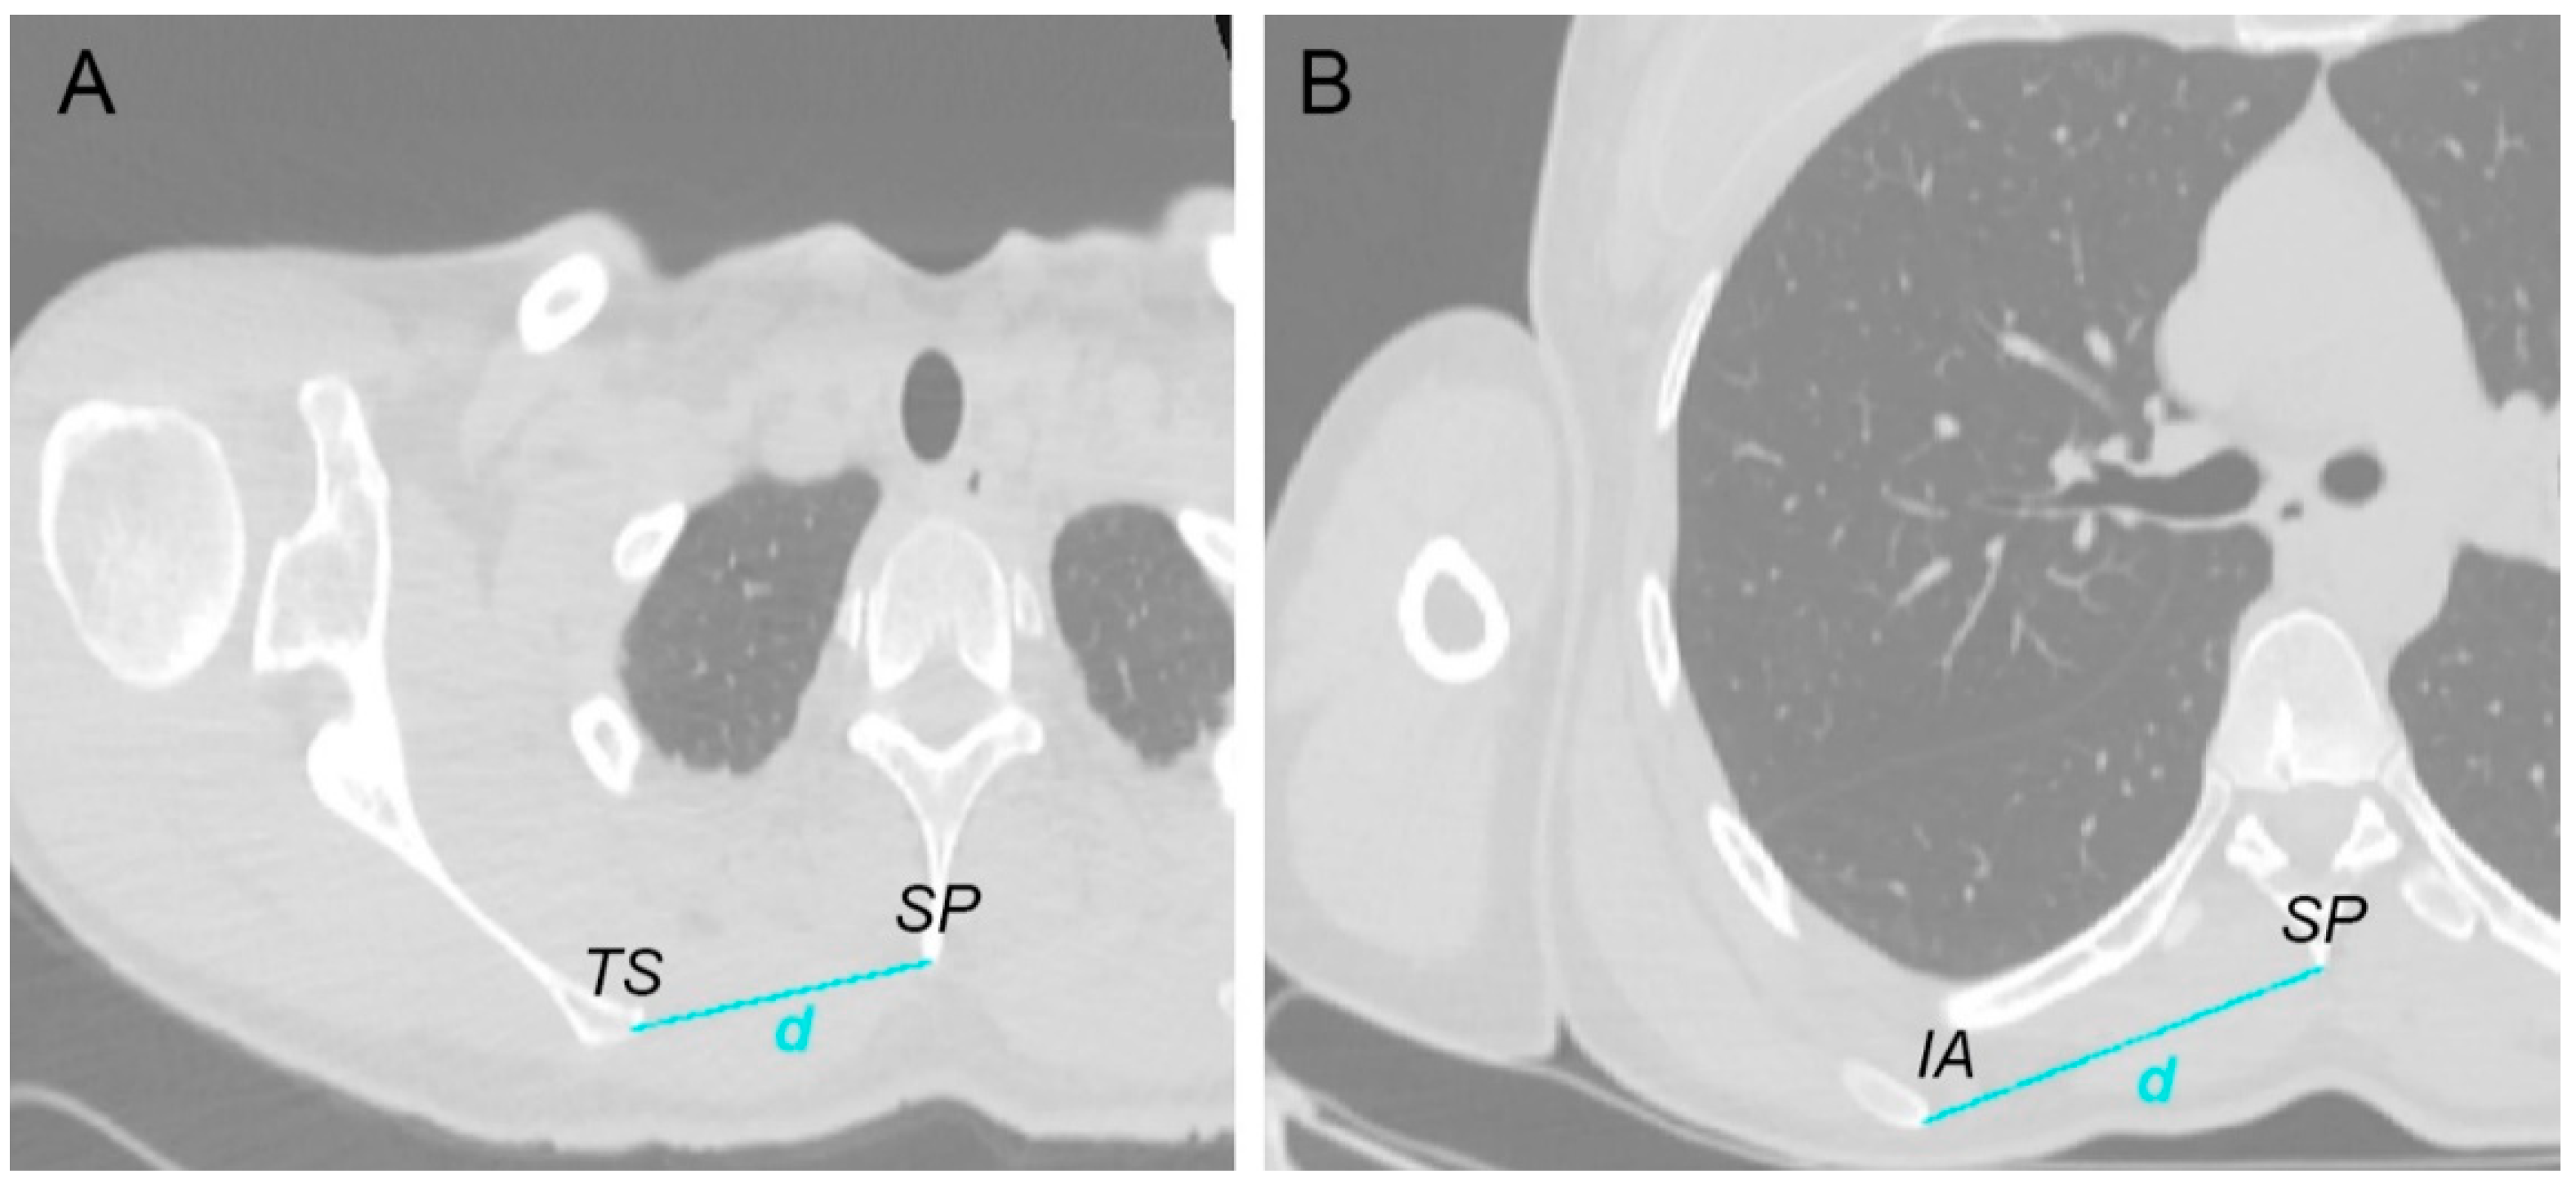

2.5. Scapula Positioning Relative to the Thorax

| At the trigonum spinae region | 77.7 ± 10.7 | 74.2 | (62.9–95.7) | 74.6 ± 14.9 | 67.4 | (62.5–103.5) | 0.583 |

| At the inferior scapula angle region | 107.9 ± 12.3 | 108.7 | (82.1–119.6) | 102.1 ± 18.5 | 103.1 | (78.0–134.1) | 0.466 |